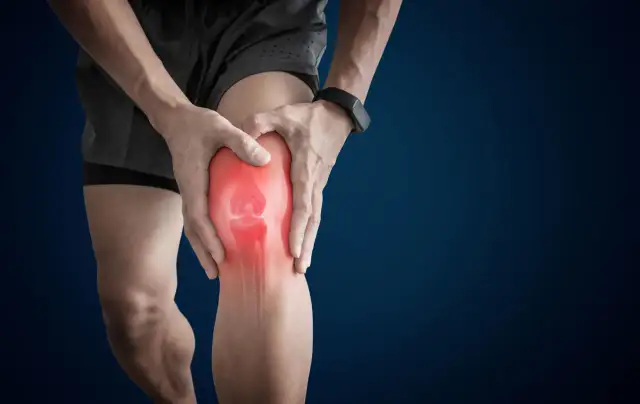

Zrozum, co oznacza ból nóg, jakie są jego przyczyny i objawy. Dowiedz się, kiedy warto szukać pomocy medycznej w przypadku bólu nóg.